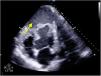

Varón 49 años ingresado tras shock cardiogénico SCAID secundario a síndrome coronario agudo sin elevación del ST de 12días de evolución no revascularizado en país de origen, complicado con disección intramiocárdica, condicionando hematoma apical contenido posterior (fig. 1, flecha amarilla), inestabilidad hemodinámica y disfunción biventricular severa que requiere de membrana de oxigenación extracorpórea veno-arterial como puente a trasplante cardiaco.